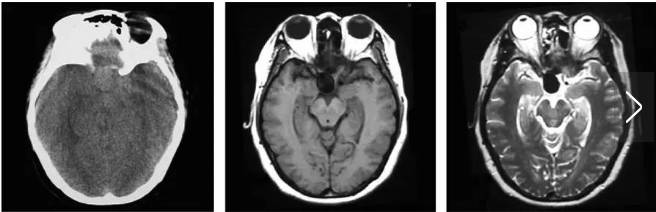

MRI表现:MRI显示动脉瘤与其血流、血栓、钙化和含铁血黄素沉积有关。无血栓动脉瘤,T1WI与T2WI均为无信号或低信号。较大的动脉瘤,由于动脉瘤内血流速度不一,血流快的部分出现“流空效应”,血流慢的部分在T1WI图像为低信号或等信号,T2WI上为高信号。动脉瘤内血栓,MRI可为高、低、等或混杂信号。增强扫描动脉瘤腔强化,血栓无明显强化。钙化和“流空”的鉴别可根据其位置,前者位于周边,,同时钙化的信号稍高于“流空”。

对怀疑蛛网膜下腔出血的患者,急性期首选CT平扫,结果为阳性时则选择CTA或MRA进一步检查。如果CTA或MRA能确定动脉瘤的存在,则可进一步行血管内介入栓塞或手术夹闭治疗。如果CTA或MRA未发现动脉瘤,需要脑血管造影进一步确诊,DSA是诊断颅内动脉瘤最可靠的检查方法。